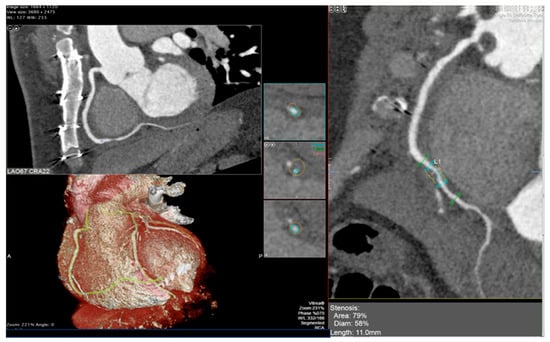

The integration of intravascular ultrasound (IVUS) with ICA reveals approximately 19% more cases of CAV, making it the most sensitive test available for monitoring CAV progression in the clinical setting [55]. However, CCTA has been proposed as an alternative to IVUS for routine follow-up of HT patients due to its superior spatial resolution [56]. In a recent meta-analysis, the sensitivity, specificity, positive predictive value, and negative predictive value of CCTA for detecting CAV were reported as 97%, 81%, 78%, and 97%, respectively [57]. Nevertheless, there is currently no standard method available for the assessment of CAV on CCTA images, and distinguishing CAV from atherosclerotic lesions can be challenging (examples in Figure 2 and Figure 3).

Figure 3. Cardiac computed tomography images showing cardiac allograft vasculopathy grade IV-A according to the International Society for Heart and Lung Classification with a non-calcific, sub occlusive coronary plaque at the second tract of the circumflex coronary artery assessed with cardiac tomography angiography.